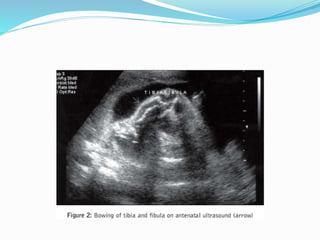

 Features mainly in the lower limb :

 1- Short bowed femur , tibia and Fibula + marked

Talipes

 2- The whole lower limb is bowed inwards hint the

name (Campomelia) derived from a greek word campo

or campto meaning BENT.

Campomelic Dysplasia  Featuresmainly in the lower limb :  1- Short bowed femur , tibia and Fibula + marked Talipes  2- The whole lower limb is bowed inwards hint the name (Campomelia) derived from a greek word campo or campto meaning BENT.  3- marked association with soft tissue involvement (cardiac, renal and Brain)

Prognosis  ¾ ofthe cases die during neonatal period due to associated pulmonary hypoplasia the prognosis is mainly dependent on other organ involvement  Recurrence is around 5%